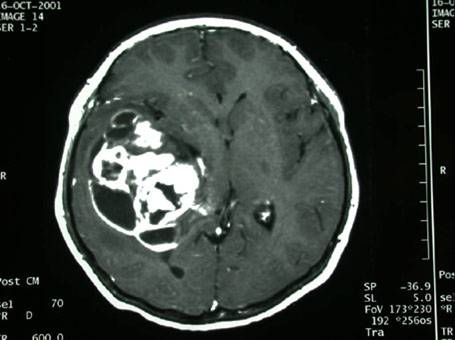

右颞深部胶质瘤

男性,40岁,主因,癫痫发作入院,查MRI示:右颞胶质瘤。

术前影像